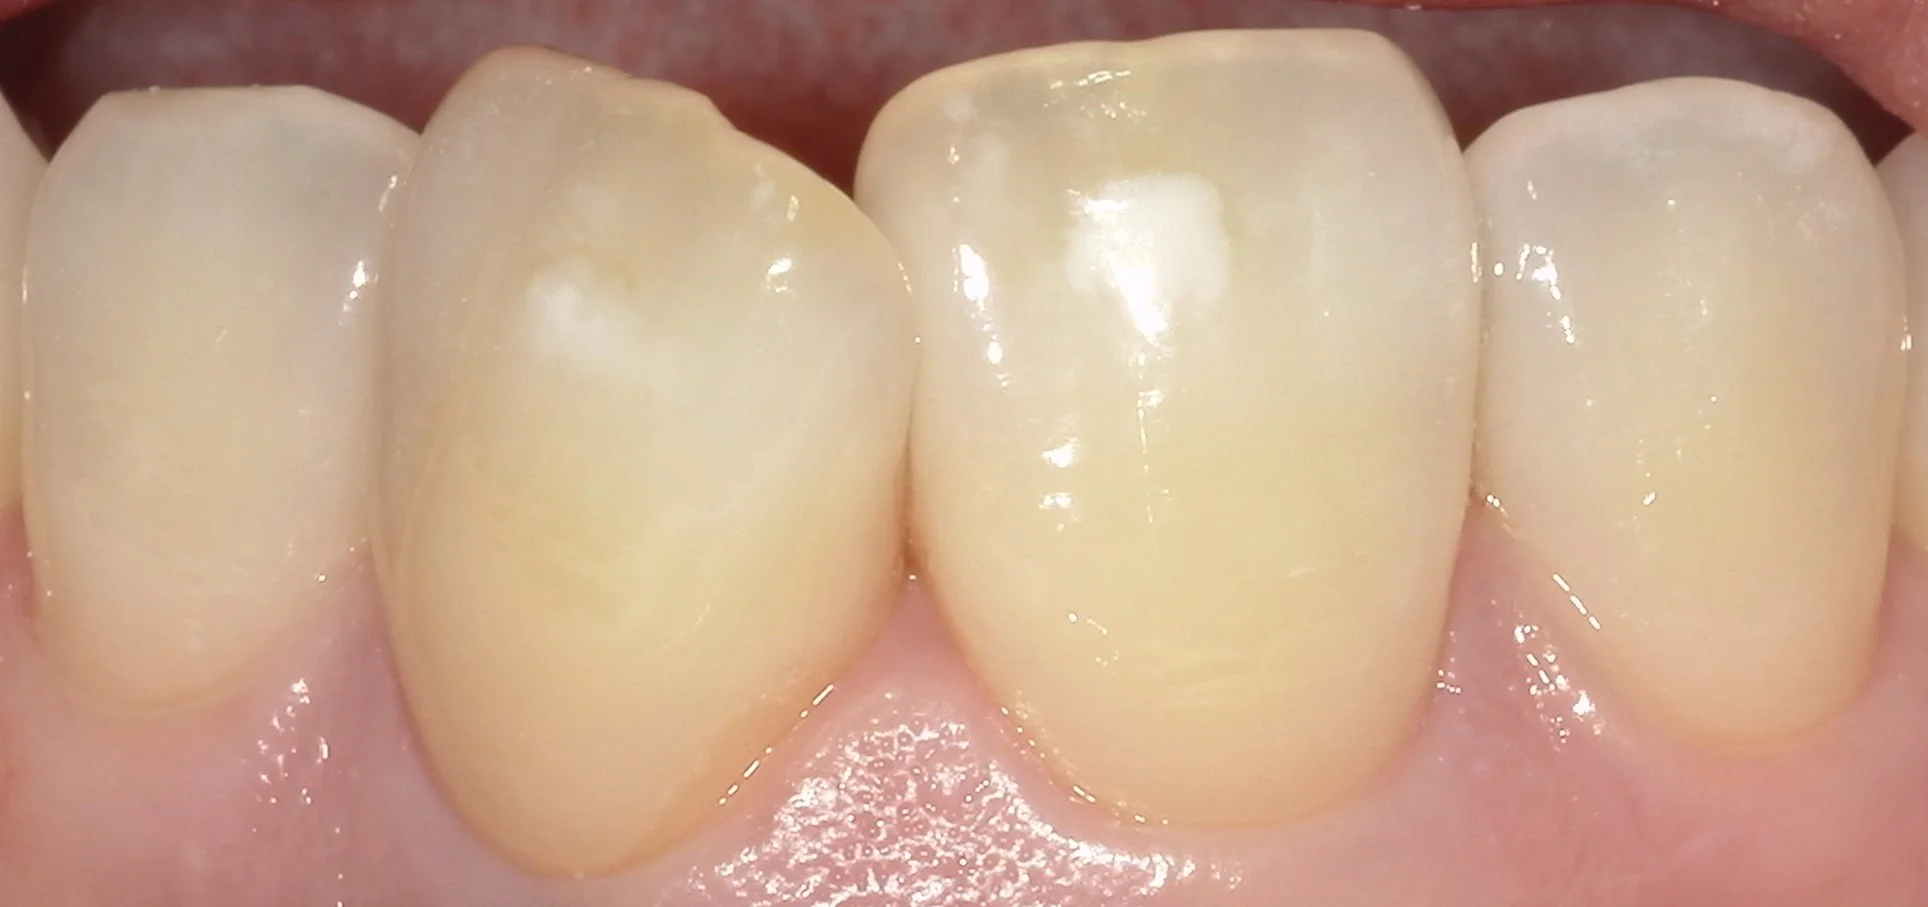

こんな感じで、歯の表面に白い点があることってありませんか?

この部分をホワイトスポットと言います。

まずは術前の状態です。

真ん中2本の歯の中央に白いホワイトスポットがあるのが分かるかと思います。